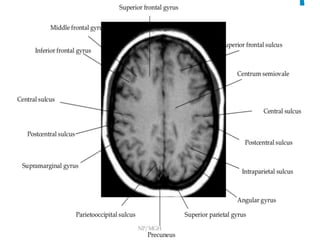

The central sulcus is separating

the precentral gyrus (motor)

from

the postcentral gyrus (sensory).

-The superior frontal sulcus is

identified between the superior

and middle frontal gyri. It

typically meets the precentral

sulcus almost at a right angle.

-Posterior to this lies the central

sulcus. The bulge in the

precentral gyrus represents the

hand motor area.

•  Hand	knob	sign	–	Dorsally	convex	bulge	of	precentral	gyrus

•  Inverted	omega	sign-	central	sulcus

Corona	radiata

Central	sulcus

Precentral	G

Corona	radiata	(centrum	semiovale)	is	formed	by	fibers	from	all	corHcal	areas	in	internal

capsule	fanning	out	into	superior	hemispheres.

•  On	axial	T2	image,	the	intraparietal	sulcus		separates

the	superior	parietal	lobule(medially)	from	the

inferior	parietal	lobule(laterally).	Anteriorly,	it

merges	with	the	post	central	sulcus.